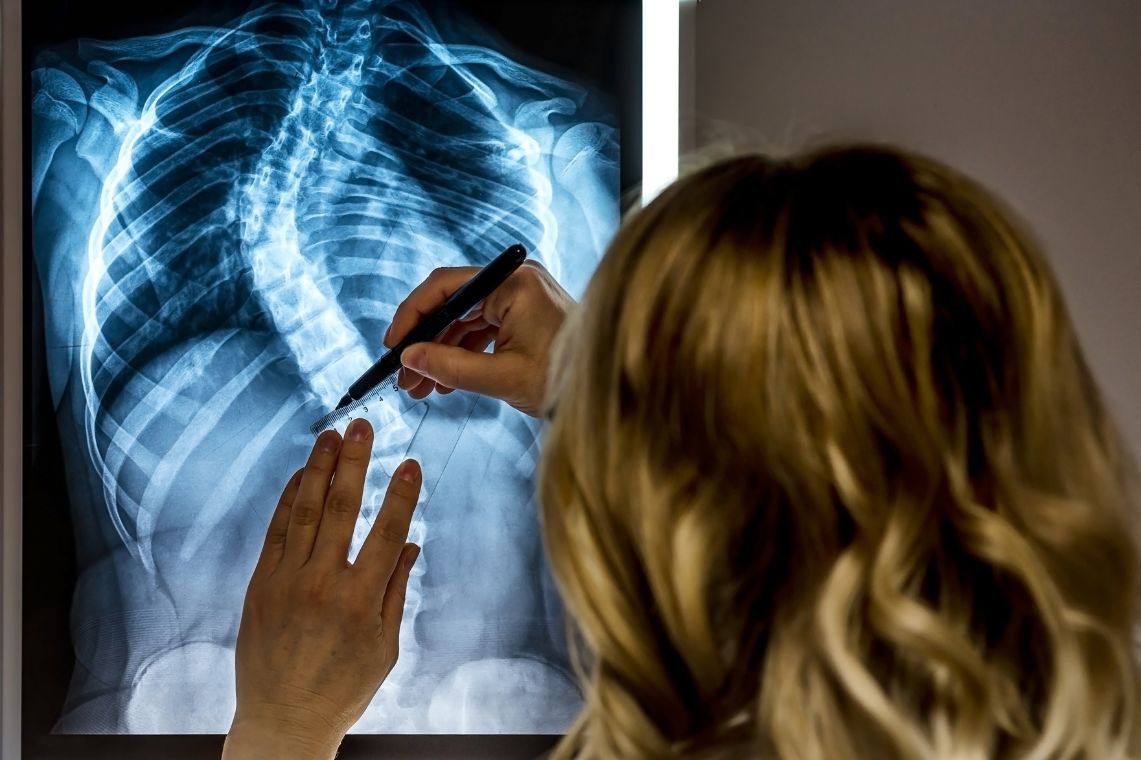

Once we are finished with the surgery, x-rays taken of your spine will show your new alignment as well as the hardware that we used.

Below are before and after photos of two of our patients who underwent a posterior spinal fusion, one for scoliosis and one for kyphosis.

Scoliosis

Kyphosis